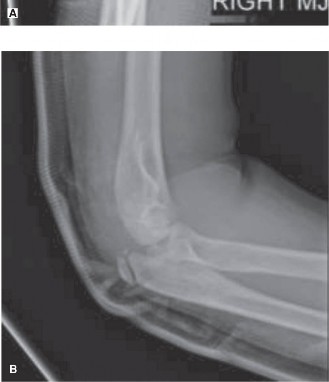

CASE 4 An 11-year-old girl was transferred from an outside hospital for further evaluation and treatment. Earlier that day, she had been at a gymnastics meet when, upon dismount, she over-rotated and landed on her arm rather than sticking the landing. She had immediate pain and gross deformity of her elbow. She was transported to her local emergency room. An orthopaedic surgeon was called in after x-rays confirmed elbow dislocation. The surgeon performed a reduction in the ER and then splinted the elbow. Postreduction x-rays were obtained (Fig. 10–5A and B) and revealed the following.

Figure 10–5 A–B

The correct answer is (E). The radiographs of the elbow demonstrate an incarcerated medial epicondyle. Medial epicondyle fractures occur from a valgus stress across the elbow. About 50% are associated with an elbow dislocation. The flexor-pronator mass originates on the medial epicondyle and, with a valgus force across the elbow, can avulse the medial epicondyle off the humerus. If there is a dislocation, sometimes with reduction, the medial epicondyle is pulled into the joint and becomes incarcerated. An incarcerated medial epicondyle is the undisputed indication for surgical intervention for a medial epicondyle fracture. Open reduction with screw fixation (usually with a washer) is the preferred method of treatment as it allows for early motion. Percutaneous pinning is an option for young children. Casting is an option if the fracture is not incarcerated, the elbow is stable, and there is not significant displacement (amount of displacement that indicates operative intervention remains controversial).